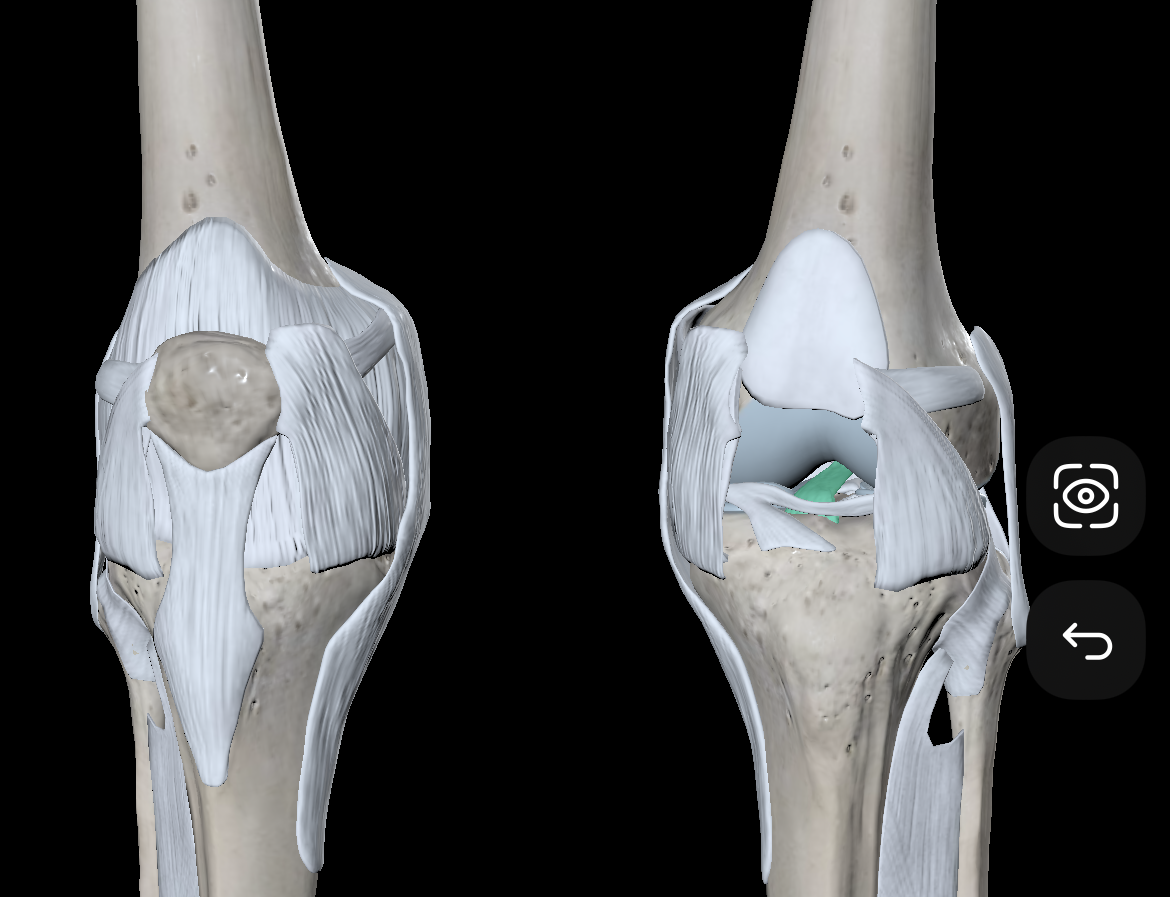

Medial Condyles of the Femur

Lateral Condyles of the Femur

Medial Epicondyles of the Femur

Lateral Epicondyles of the Femur

Medial Tibial Condyles

Lateral Tibial Condyles

Anterior Cruciate Ligament

Posterior Cruciate Ligament